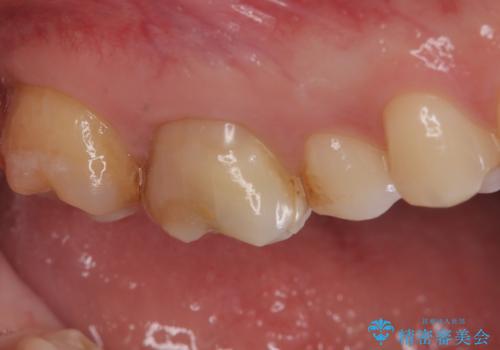

【奥歯のセラミッククラウン】他院で根管治療も必要だといわれた。

- 他院で歯の根っこの先端に膿が溜まっているため治療が必要だといわれた患者様です。

根っこの治療を顕微鏡を見ながら行ってくれる医院を探して当院に来院されました。

以前治療した際のむし歯が大きく、長い年月の間に少しずつ歯髄が死んでしまったと思われる状況でした。

長期にわたる炎症により、口蓋根尖は吸収を起こしていたため、MTAにて充填しています。